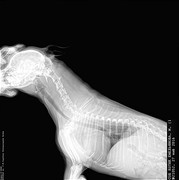

Коллапс трахеи форум